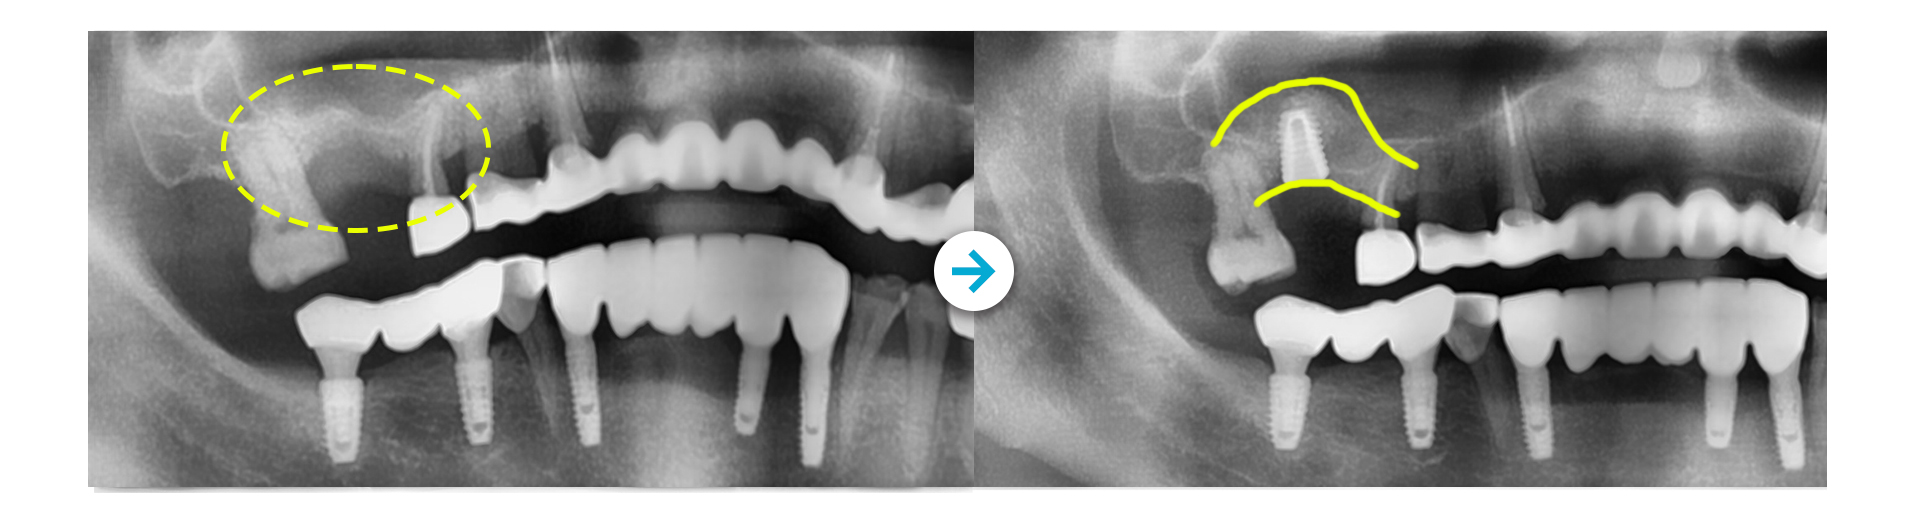

미소가득 뼈이식 임플란트 CASE ]

상악동 거상술 후 임플란트 식립

Before 사진 촬영일자: 2017.01.25 /  After 사진 촬영일자: 2017.02.06

Before 사진 촬영일자: 2025.10.27 /  After 사진 촬영일자: 2026.01.07